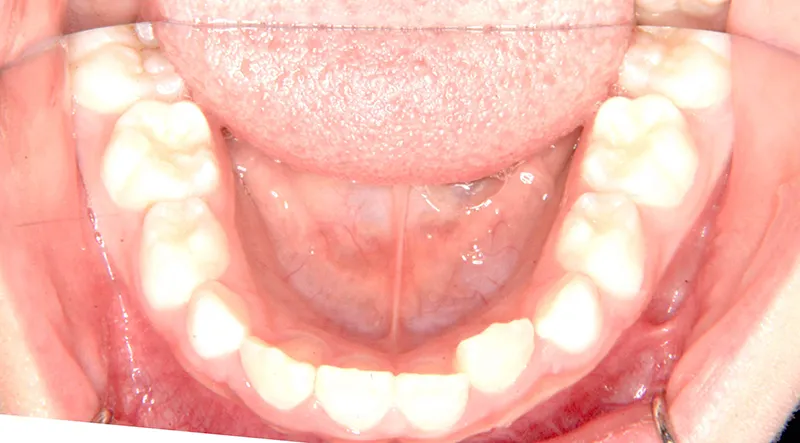

| 初診時年齢 | 小学校1年生(女性) | 主訴 | 受け口 | ||

| 診断名 | 叢生・反対咬合 | 装置名 | 拡大床 | ||

| 抜歯の有無 | 非抜歯 | 治療期間・通院回数 | 2年7ヶ月・21回 | ||

| 費用 | 481,890円(税込) | 費用内訳 | 相談料:1,050円 検査料:46,200円 施術料:210, 000円 装置料:105,000円 保定装置料:52,500円 調整料:3,150円×10回=31,500円 以上 消費税率5% / 調整料:3,240円×11回=35,640円 以上 消費税率8% | ブラケット・ ワイヤー |

付けずに治した |

| 特徴 |

固い食べ物が嫌い 乳歯列が綺麗に並んでいる ゆがんで生えている よく噛まないで飲み込む |

| 状態 |

永久歯が生える隙間がない(叢生) 受け口(口元が出ている/下顎前突/反対咬合) |

| リスク・副作用 |

矯正歯科治療に伴う一般的なリスク・副作用

|